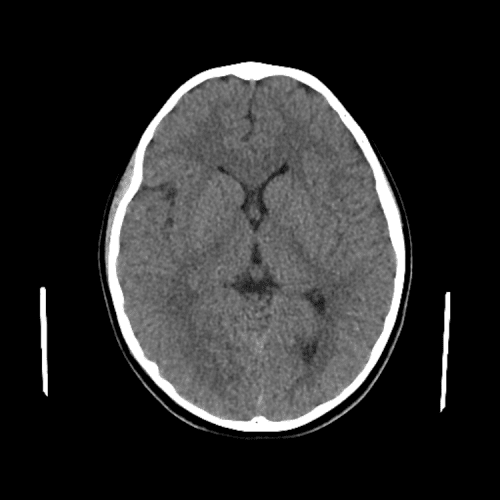

Deep venous infarct